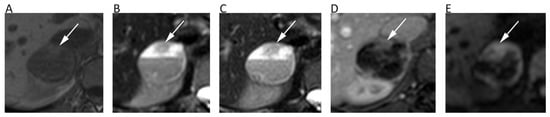

6. Hepatobiliary

| Hepatobiliary | Miller, F.H.; et al. J. Magn. Reson. Imaging 2010 [32] | Retrospective; 542 focal liver lesions in 382 patients; 1.5T MRI. | Mean ADC (10−3 mm2/s) of hemangiomas = 2.26, FNH = 1.79, adenomas = 1.49, abscesses = 1.97, HCC = 1.53, and metastases = 1.50. Mean ADC of benign lesions = 2.50, malignant lesions = 1.52. Overlap reported between solid benign and malignant lesions. |